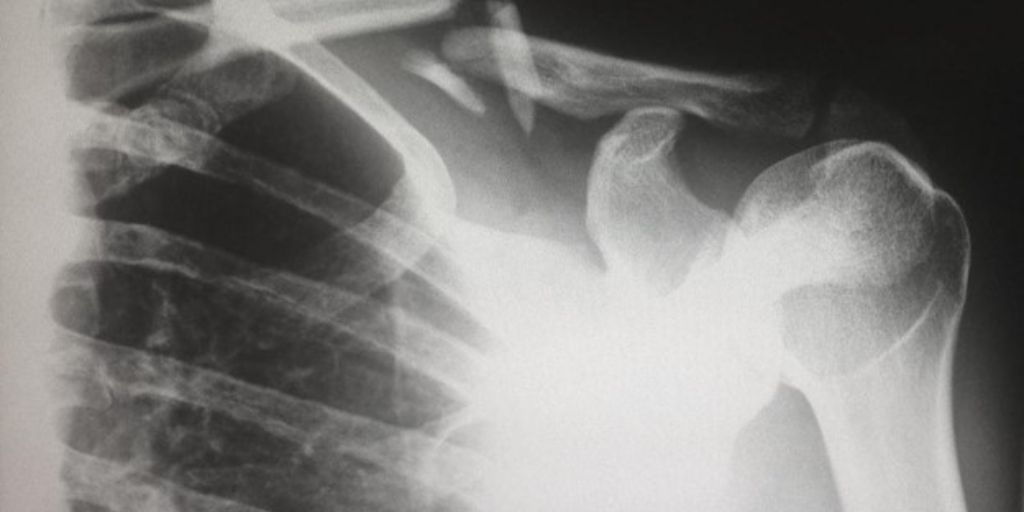

Not only this but AI has a significant edge over humans in diagnostic speed and accuracy in almost all aspects of healthcare, owing to their ability to rapidly absorb, analyze, and then arrive at conclusions based on sets of provided data. Additionally, AI algorithms are capable of examining X-rays, MRI scans, and more, to identify certain characteristics that a tired, overworked, or inattentive doctor might miss.